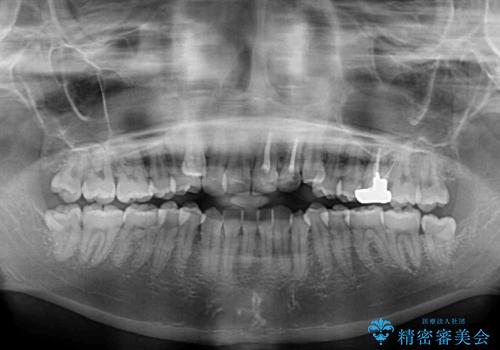

- 上の八重歯を気にして来院された患者様です。

受け口傾向にあるため、上顎前歯の叢生解消とともに下顎前歯を後方へ移動させることを目的とし、上下左右の第一小臼歯4歯を抜歯することとしました。